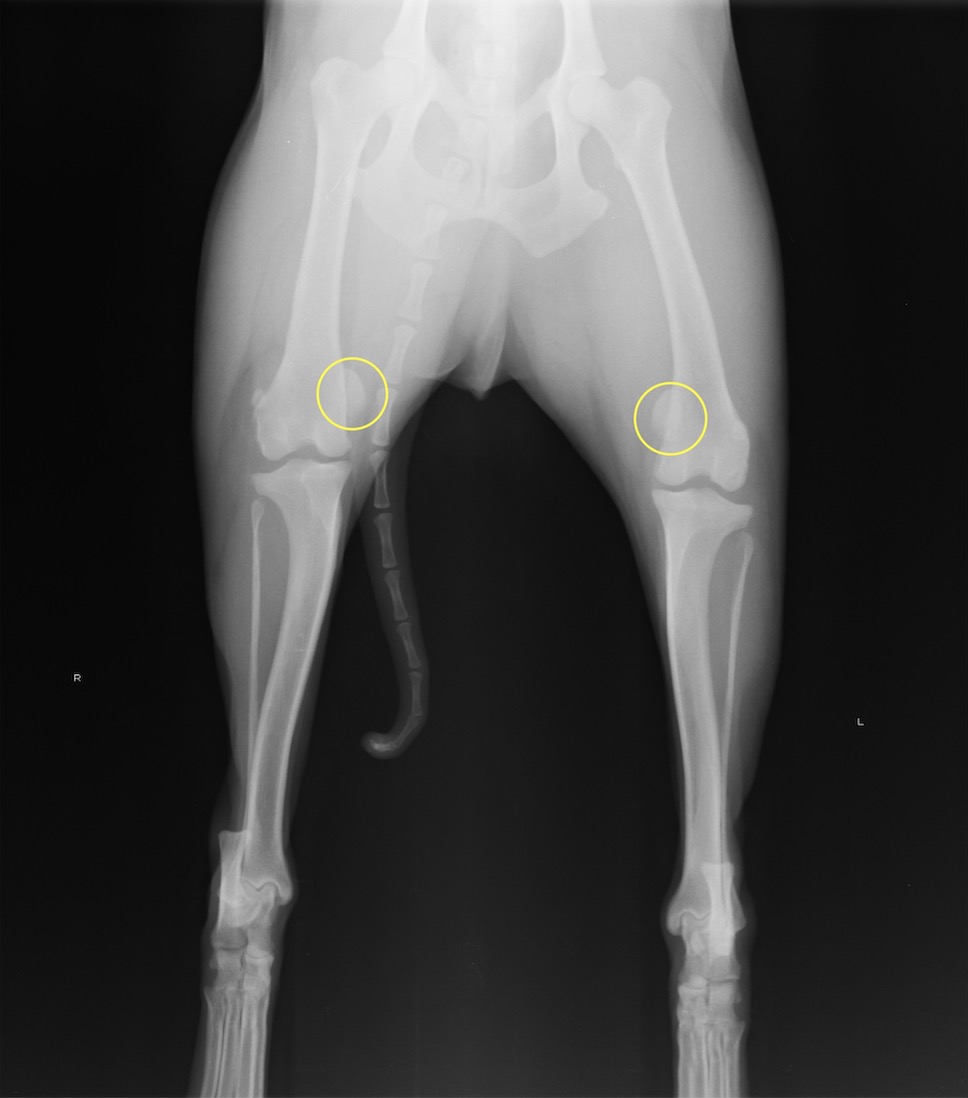

本症例は両側膝蓋骨内方脱臼GradeIIIと診断されました。膝蓋骨が明らかに内側へ脱臼しております。

術後のレントゲン写真